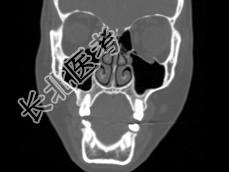

- 多项选择题女,25岁, 车祸伤及面部,X线及CT检查如图所示, 正确的描述或诊断是 ( )

A、X线示左侧眶底较正常变低

B、CT发现左侧眶底骨质断裂

C、左侧上颌窦内见气-液面

D、左侧眶底骨折

E、左侧上颌窦积液